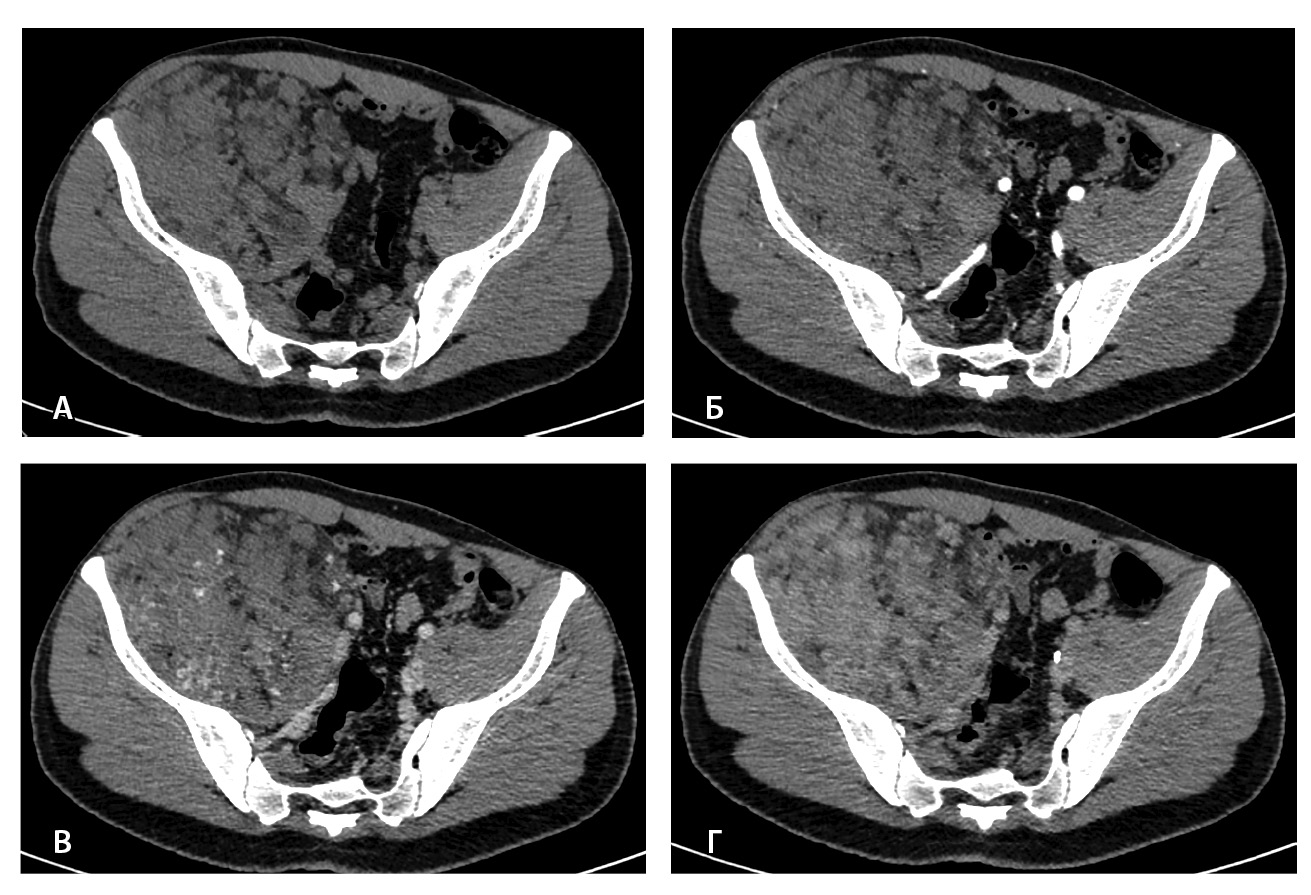

Результаты дооперационной мультиспиральной компьютерной томографии органов брюшной полости и забрюшинного пространства (рис. 1, 2): «В забрюшинном пространстве справа визуализируется образование, исходящее из подвздошно-поясничной мышцы, с выходом вдоль сосудистого пучка на верхнюю треть бедра. Образование с четкими и ровными контурами, размерами 145 × 125 × 125 мм. Структура образования гетерогенная, плотность в нативную фазу исследования от –40 до 50 HU, содержит единичные кальцинаты, жировую ткань и мягкотканный компонент. На фоне контрастирования в артериальную и венозную фазы в структуре выявляются извитой формы участки гиперконтрастирования (сосудистая сеть). Максимальное накопление контрастного препарата происходит преимущественно к отсроченной фазе исследования. Усредненные плотностные характеристики составляют 25, 36, 53 и 59 HU в нативную, артериальную, венозную и отсроченную фазы соответственно. Опухоль оттесняет тазовую брюшину, правую подвздошно-поясничную мышцу, илеоцекальный угол кпереди. Образование тесно прилежит сзади к крылу правой подвздошной кости и лобковой кости, спереди – к прямой и внутренней косым мышцам живота, верхним контуром – к поясничной мышце. Медиально в средней трети по контуру образования проходят правые наружные и внутренние подвздошные сосуды, со сдавлением наружной подвздошной вены. Данных за распространение на прилежащие внутренние органы и клетчатку не получено. Кости без деструктивных изменений».

Рис. 1. Мультиспиральная компьютерная томография органов брюшной полости и забрюшинного пространства с болюсным внутривенным контрастированием: А – нативная фаза, Б – артериальная фаза, В – венозная фаза, Г – отсроченная фаза. Крупное гетерогенной структуры образование забрюшинного пространства справа, с фокусами гиперваскуляризации в структуре. Тесно прилежит к крылу подвздошной кости и подвздошным сосудам, оттесняя последние медиально

При контрольной томографии, проведенной на 5-е сутки после операции, забрюшинно справа определялась остаточная ткань опухоли размерами 125 × 81 × 90 мм. Резидуальный фрагмент прилегал к правой подвздошной кости, по ходу подвздошных сосудов, с распространением на переднюю поверхность правого бедра. Признаков экстравазации контрастного препарата не обнаружено (рис. 3).

Рис. 3. Мультиспиральная компьютерная томография органов брюшной полости и забрюшинного пространства с болюсным внутривенным контрастированием, венозная фаза. А – исследование до операции, Б – исследование после операции: резидуальный фрагмент образования (красная стрелка) тесно прилежит к подвздошной кости и подвздошным сосудам (головка синей стрелки)